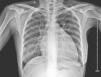

Physical examination revealed blood pressure of 130/90mmHg, heart rate of 122/min, a dilated jugular vein, and an audible gallop rhythm and systolic ejection murmur. There was mild peripheral edema. Chest radiography showed an enlarged and globular cardiac silhouette and pulmonary congestion without pleural effusion (Fig. 1). Serum free T3, T4, total T3, T4 and thyroid stimulating hormone (TSH) were within normal values with levothyroxine replacement therapy at a dose of 50μg daily. Cardiac enzymes, liver enzymes, erythrocyte sedimentation rate and C reactive protein were normal. Antinuclear, antithyroperoxidase and antithyroglobulin antibodies were positive. Rheumatoid factor and anti-α-myosin antibodies were absent. Coxsackie virus, Chlamydia pneumoniae and Mycoplasma pneumoniae serology were negative. Echocardiography showed decreased left ventricular systolic function with an ejection fraction (EF) of 32% and fractional shortening (FS) of 15%, as well as dilated left ventricle with decreased wall motion of entire left ventricle (Fig. 2). Dilated cardiomyopathy and hypothyroidism secondary to Peg IFNα-2a was suspected. Therefore, Peg IFN-α and ribavirin was discontinued after 23 weeks of treatment. The patient was treated with Benazepril, Digoxin, Furosemide, Metoprolol Succinate and Levothyroxine. Her symptoms improved in one week and she was discharged on the same medications. A second echocardiogram three months later showed an EF of 47% with normal chambers, and heart failure medications were discontinued. She maintained normal aminotransferases and undetectable HCV RNA after 24 months of follow up. However, she needs permanent thyroid hormone replacement therapy for hypothyroidism.